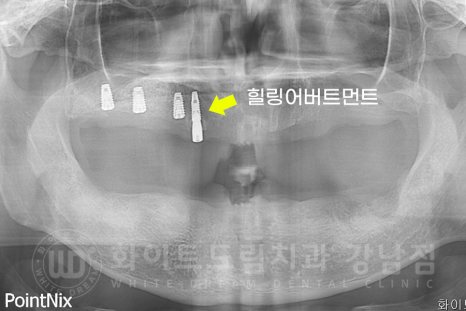

초기 임플란트를 식립하고 고정력이 좋은 임플란트들은 모두

1차 + 2차 수술을 같이 진행했습니다.

▲ 노란색으로 표기된 부분이 1+2차 수술을 동시 진행한 임플란트입니다. (상악)

1차 수술은 임플란트를 잇몸뼈 안에 심는 것이고,

2차 수술은 보철을 부착할 수 있도록 잇몸 밖으로 꺼내는 술식입니다.

이 1차, 2차 수술을 동시에 진행하면, 따로 2차 수술을 진행할 필요가 없기 때문에

기간과 내원 횟수가 줄어드는 장점을 가지고 있죠.

▲ 노란색으로 표기된 부분이 1+2차 수술을 동시 진행한 임플란트입니다. (하악)

상악동 거상술을 진행한 부위를 제외하고 거의 모든 임플란트를 이 방식으로 진행했습니다.